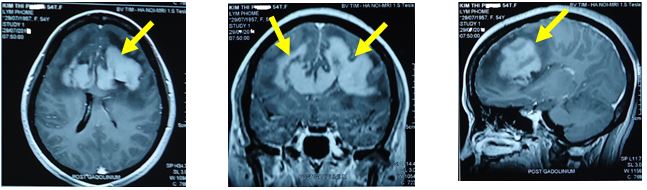

Bệnh nhân tiếp tục được hội chẩn xạ phẫu bằng dao gamma quay vào u não còn lại với liều 14Gy.

Đánh giá kết quả sau điều trị xạ phẫu:

- Về lâm sàng: sau 3 tháng điều trị bệnh nhân không còn đau đầu, không liệt vận động, các sinh hoạt trở lại bình thường.

- Về hình ảnh MRI sọ não:

Hình 3. Tổn thương u não so sánh trước và sau điều trị trên hình ảnh MRI sọ não.